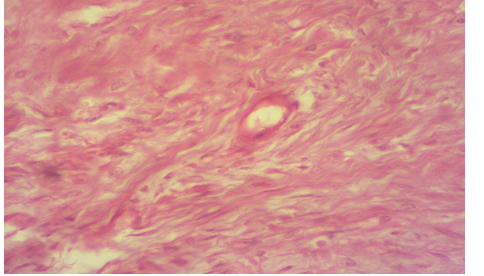

Photomicrography of T2 group at 30th post operation showed irregular connective tissue with presence of epithelial cell with high collagen level (H&E 100X)